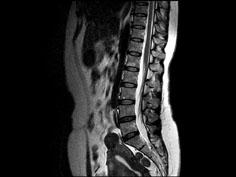

问题 女,37岁,下腹部不适,MRI检查如图所示,下列说法不正确的是 ( )

选项 A、此为子宫粘膜下肌瘤 B、此为子宫浆膜下肌瘤 C、病灶T1信号与子宫肌的信号相同 D、病灶T2信号为明显低信号 E、子宫底部局部隆起,该病灶边界清晰

答案 A